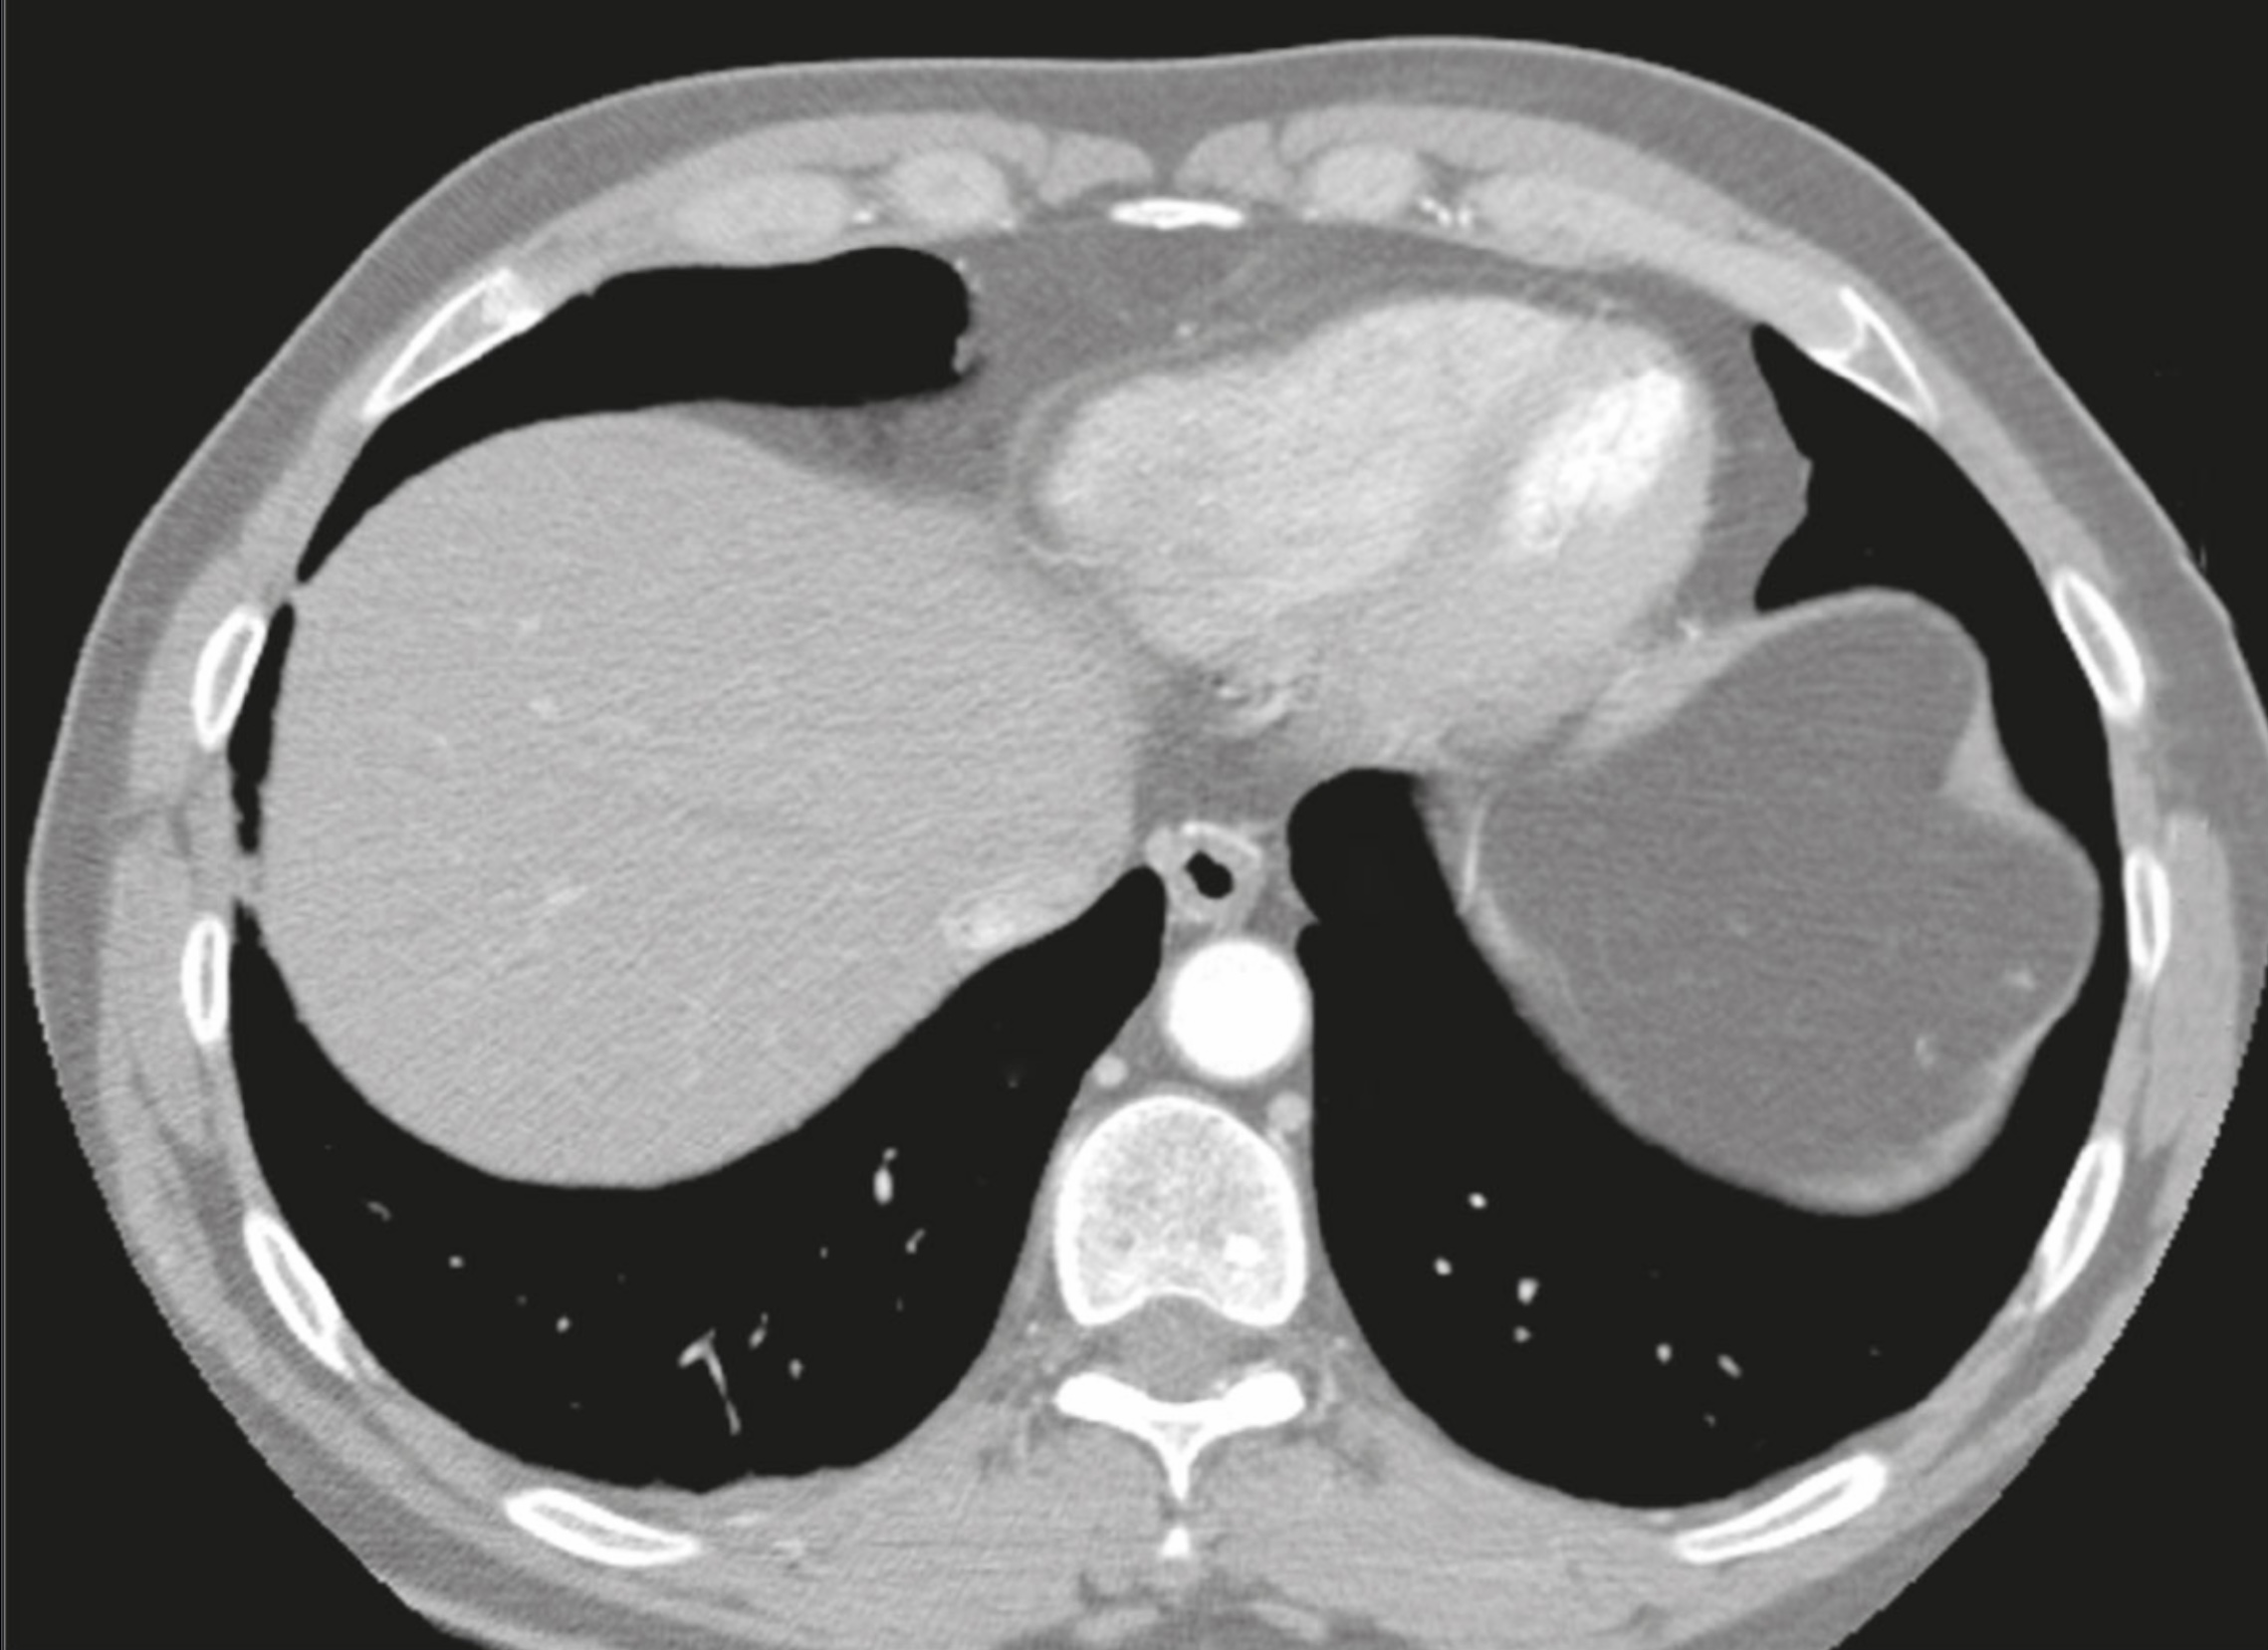

1. An 63 year old man has a heart arrhythmia. Upon further investigation, an angiogram shows an occlusion of the proximal right coronary artery. Why would this potentially cause arrhythmia? Discuss the anatomy and relationships of the right coronary artery and branches as well as the complementary venous drainage. Include mention of any commonly seen anatomical variances, if any.

2. A patient is shown to have a partial occlusion of their anterior interventricular artery (left anterior descending artery). Discuss the anatomy and relationships of the left coronary artery and branches as well as the complementary venous drainage. Why is an occlusion in this artery especially dangerous and what potential surgical solutions can be used as treatment? Include mention of commonly seen anatomical variances, if any.